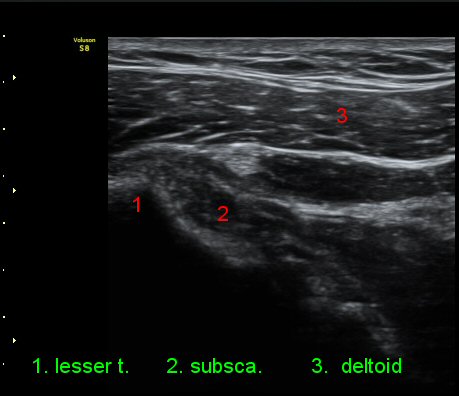

ÃÊÀ½ÆÄ °Ë»ç

3°³¿ù ÈÄ ÃßÀû°Ë»ç

2049205267_e81a53aa_US181338113.jpg